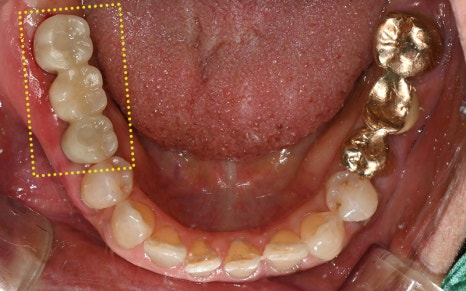

In the end, we placed the crown (prosthesis)

and successfully completed the treatment!

💕 Before > After 💕

2025.02.13 ㅡ> 2025.06.11